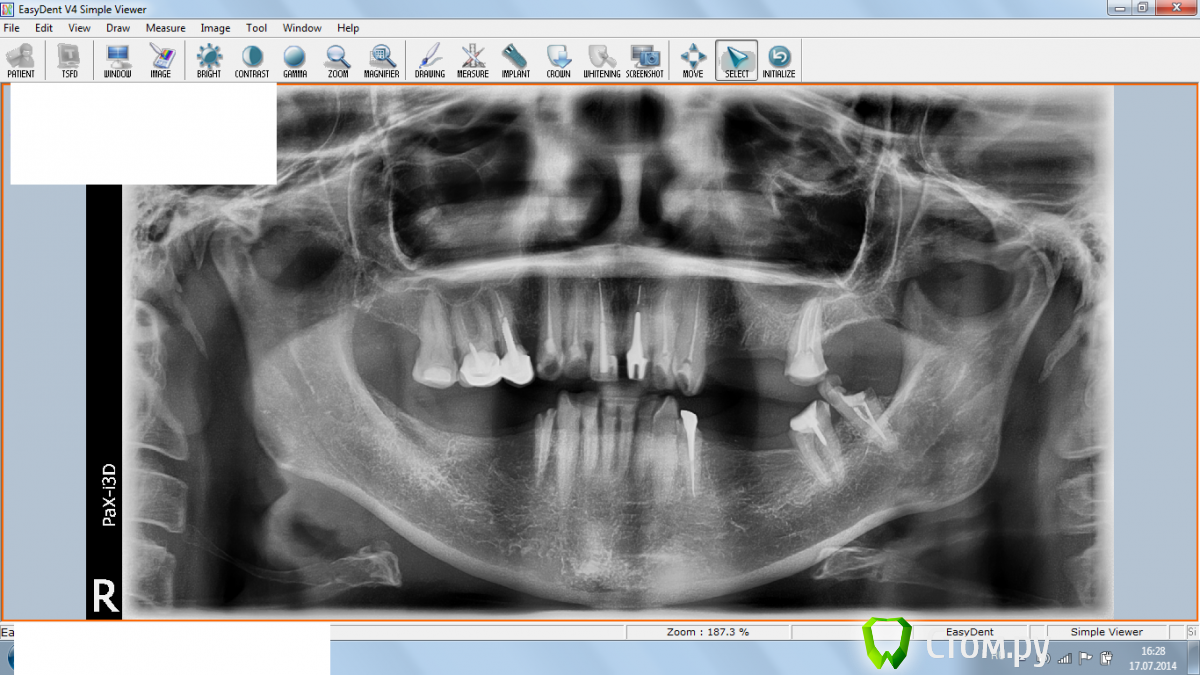

Предстоит полное протезирование.

Сняли старые мосты, удалили то, что уже нельзя было спасти.

Депульпировали передние зубы.

Сейчас осталось то, что осталось. Пока по удалению вопрос не стоит.

Но у меня с правой стороны, не то чтобы болит, а как-то ноет. Причем не могу понять, то ли вверху то ли внизу, так как отчетливой боли нет. Справа внизу там остался один корень, если болит то он. Есть показания на его удаление?

Вверху два зуба под коронками и два недавно депульпировали. Может из них "кто"?

Посмотрите пожалуйста хорошо ли запломбированы каналы, нужно что-то переделывать и есть  ли зубы на удаление? Что-то можно сказать по этому поводу?

Здравствуйте! Я бы рекомендовал зуб 3.8 (восьмерка слева) к удалению,и перелечивать корневые каналы в зубах ( вероятно,во всех, но нужны прицельные снимки). Ныть справа может как шестёрка ,так и пятёрка,оба могут являться причиной воспаления.

1. По поводу перелечивания корневых каналов - по снимку видно, что каналы плохие?

2. Удаление восьмерки - это нижний последний? Он как раз не беспокоит. Там воспаление?

4. Внизу справа последний уцелевший корень, что с ним на снимке? Иногда кажется что он болит.